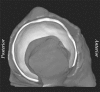

Materials and methods: Four fresh-frozen cadaver hip joints from two male donors, ages 43 and 46 years, were obtained; institutional review board approval for cadaver research was also obtained. Sixteen holes were drilled perpendicular to the cartilage of four cadaveric acetabula (two specimens). Hip capsules were surgically closed, injected with contrast material, and scanned by using multidetector CT. After scanning, 5.3-mmcores were harvested concentrically at each drill hole and cartilage thickness was measured with a microscope. Cartilage was reconstructed in 3D by using commercial software. Segmentations were repeated by two authors. Reconstructed cartilage thickness was determined by using a published algorithm. Bland-Altman plots and linear regression were used to assess accuracy. Repeatability was quantified by using the coefficient of variation, intraclass correlation coefficient (ICC), repeatability coefficient, and percentage variability.